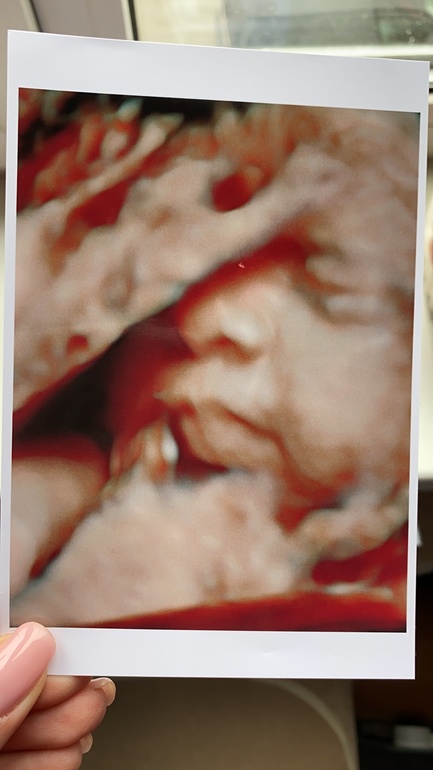

Сегодня 30+5 по овуляции. Какое же счастье, свидание прошло великолепно - большой такой мальчуган, прятался за ручкой поначалу, но потом показался 😁 лежит головушкой вниз, и девы, он такоооой большоооой!!!! Прям от лобка и выше моего пупка попка его! Обхват головки уже 30см!!! 🙈 на меня похож😁 губешки мои и носишка прямо мой😄 доктор сказала, уже волосики на головке😂😂😂 божемой, такой большой уже!!! По узи весит уже 1750гр. Половинка моей собаки🤣

Фото на память😄

Развитие без особенностей, всё по сроку, без патологий. Тьфу тьфу тьфу.

Плацента 1 степени зрелости, ИАЖ 147😊 Шейка 32мм, внутренний зев закрыт